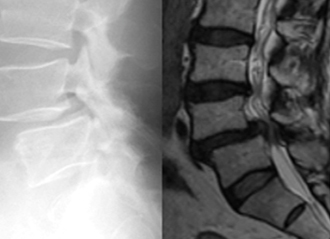

矢印が分離部で骨が離れています。

分離部に骨が移植され骨癒合が

得られています。